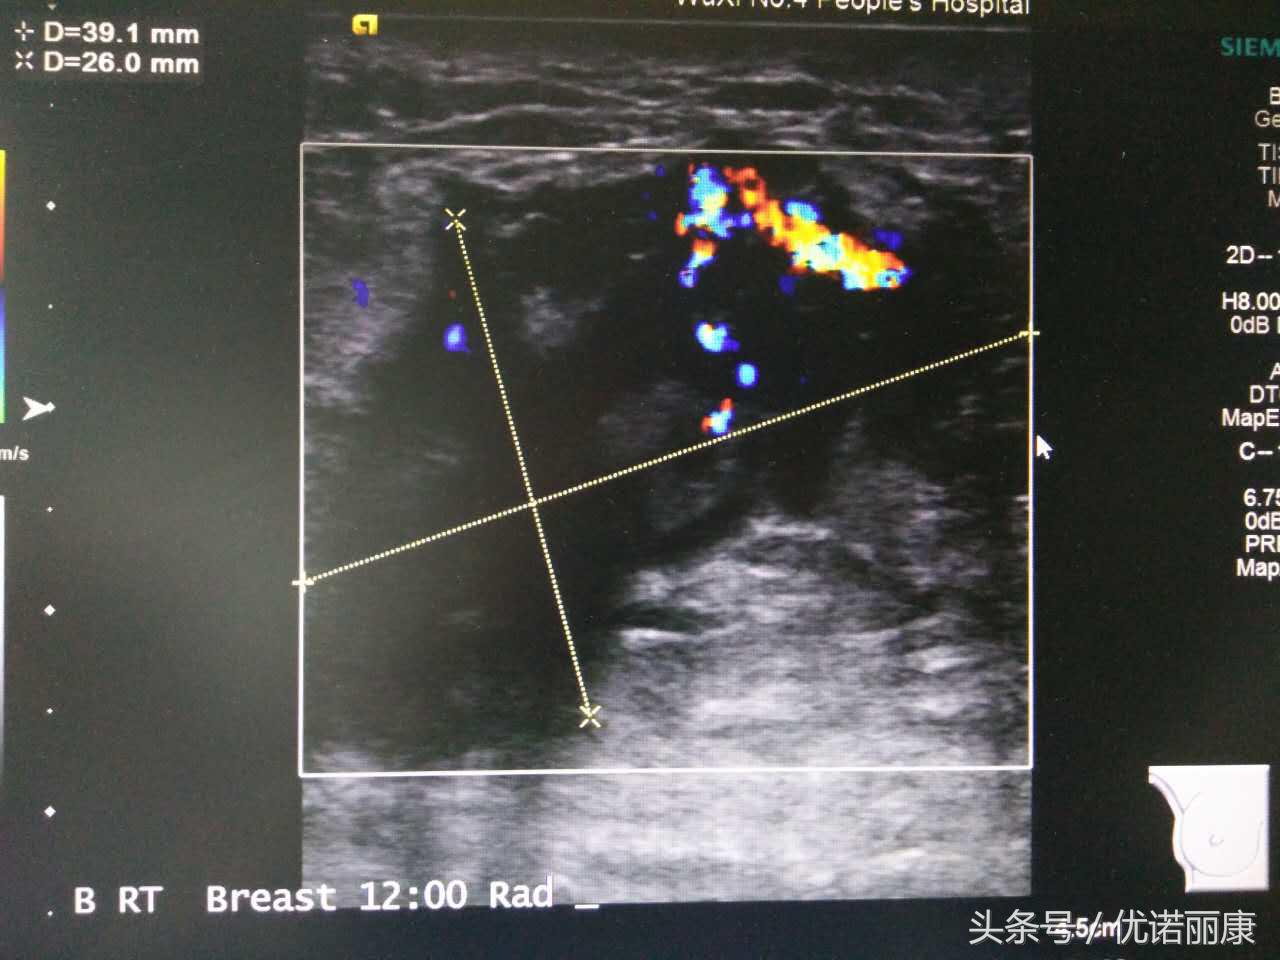

乳腺癌B超图像

肿块21x10x11mm,边界不清,形态不规则,内见强回声,钙化灶可能,内见丰富血流信号,分级5级